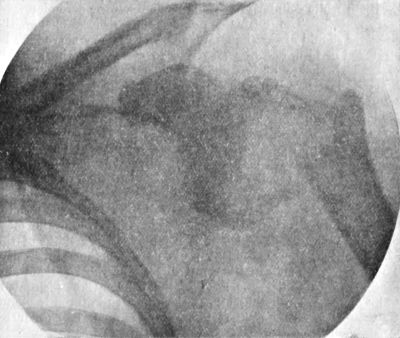

103.Arthropathy of Shoulder in Syringomyelia203

104.Radiogram of Specimen of Arthropathy of Shoulder in Syringomyelia204